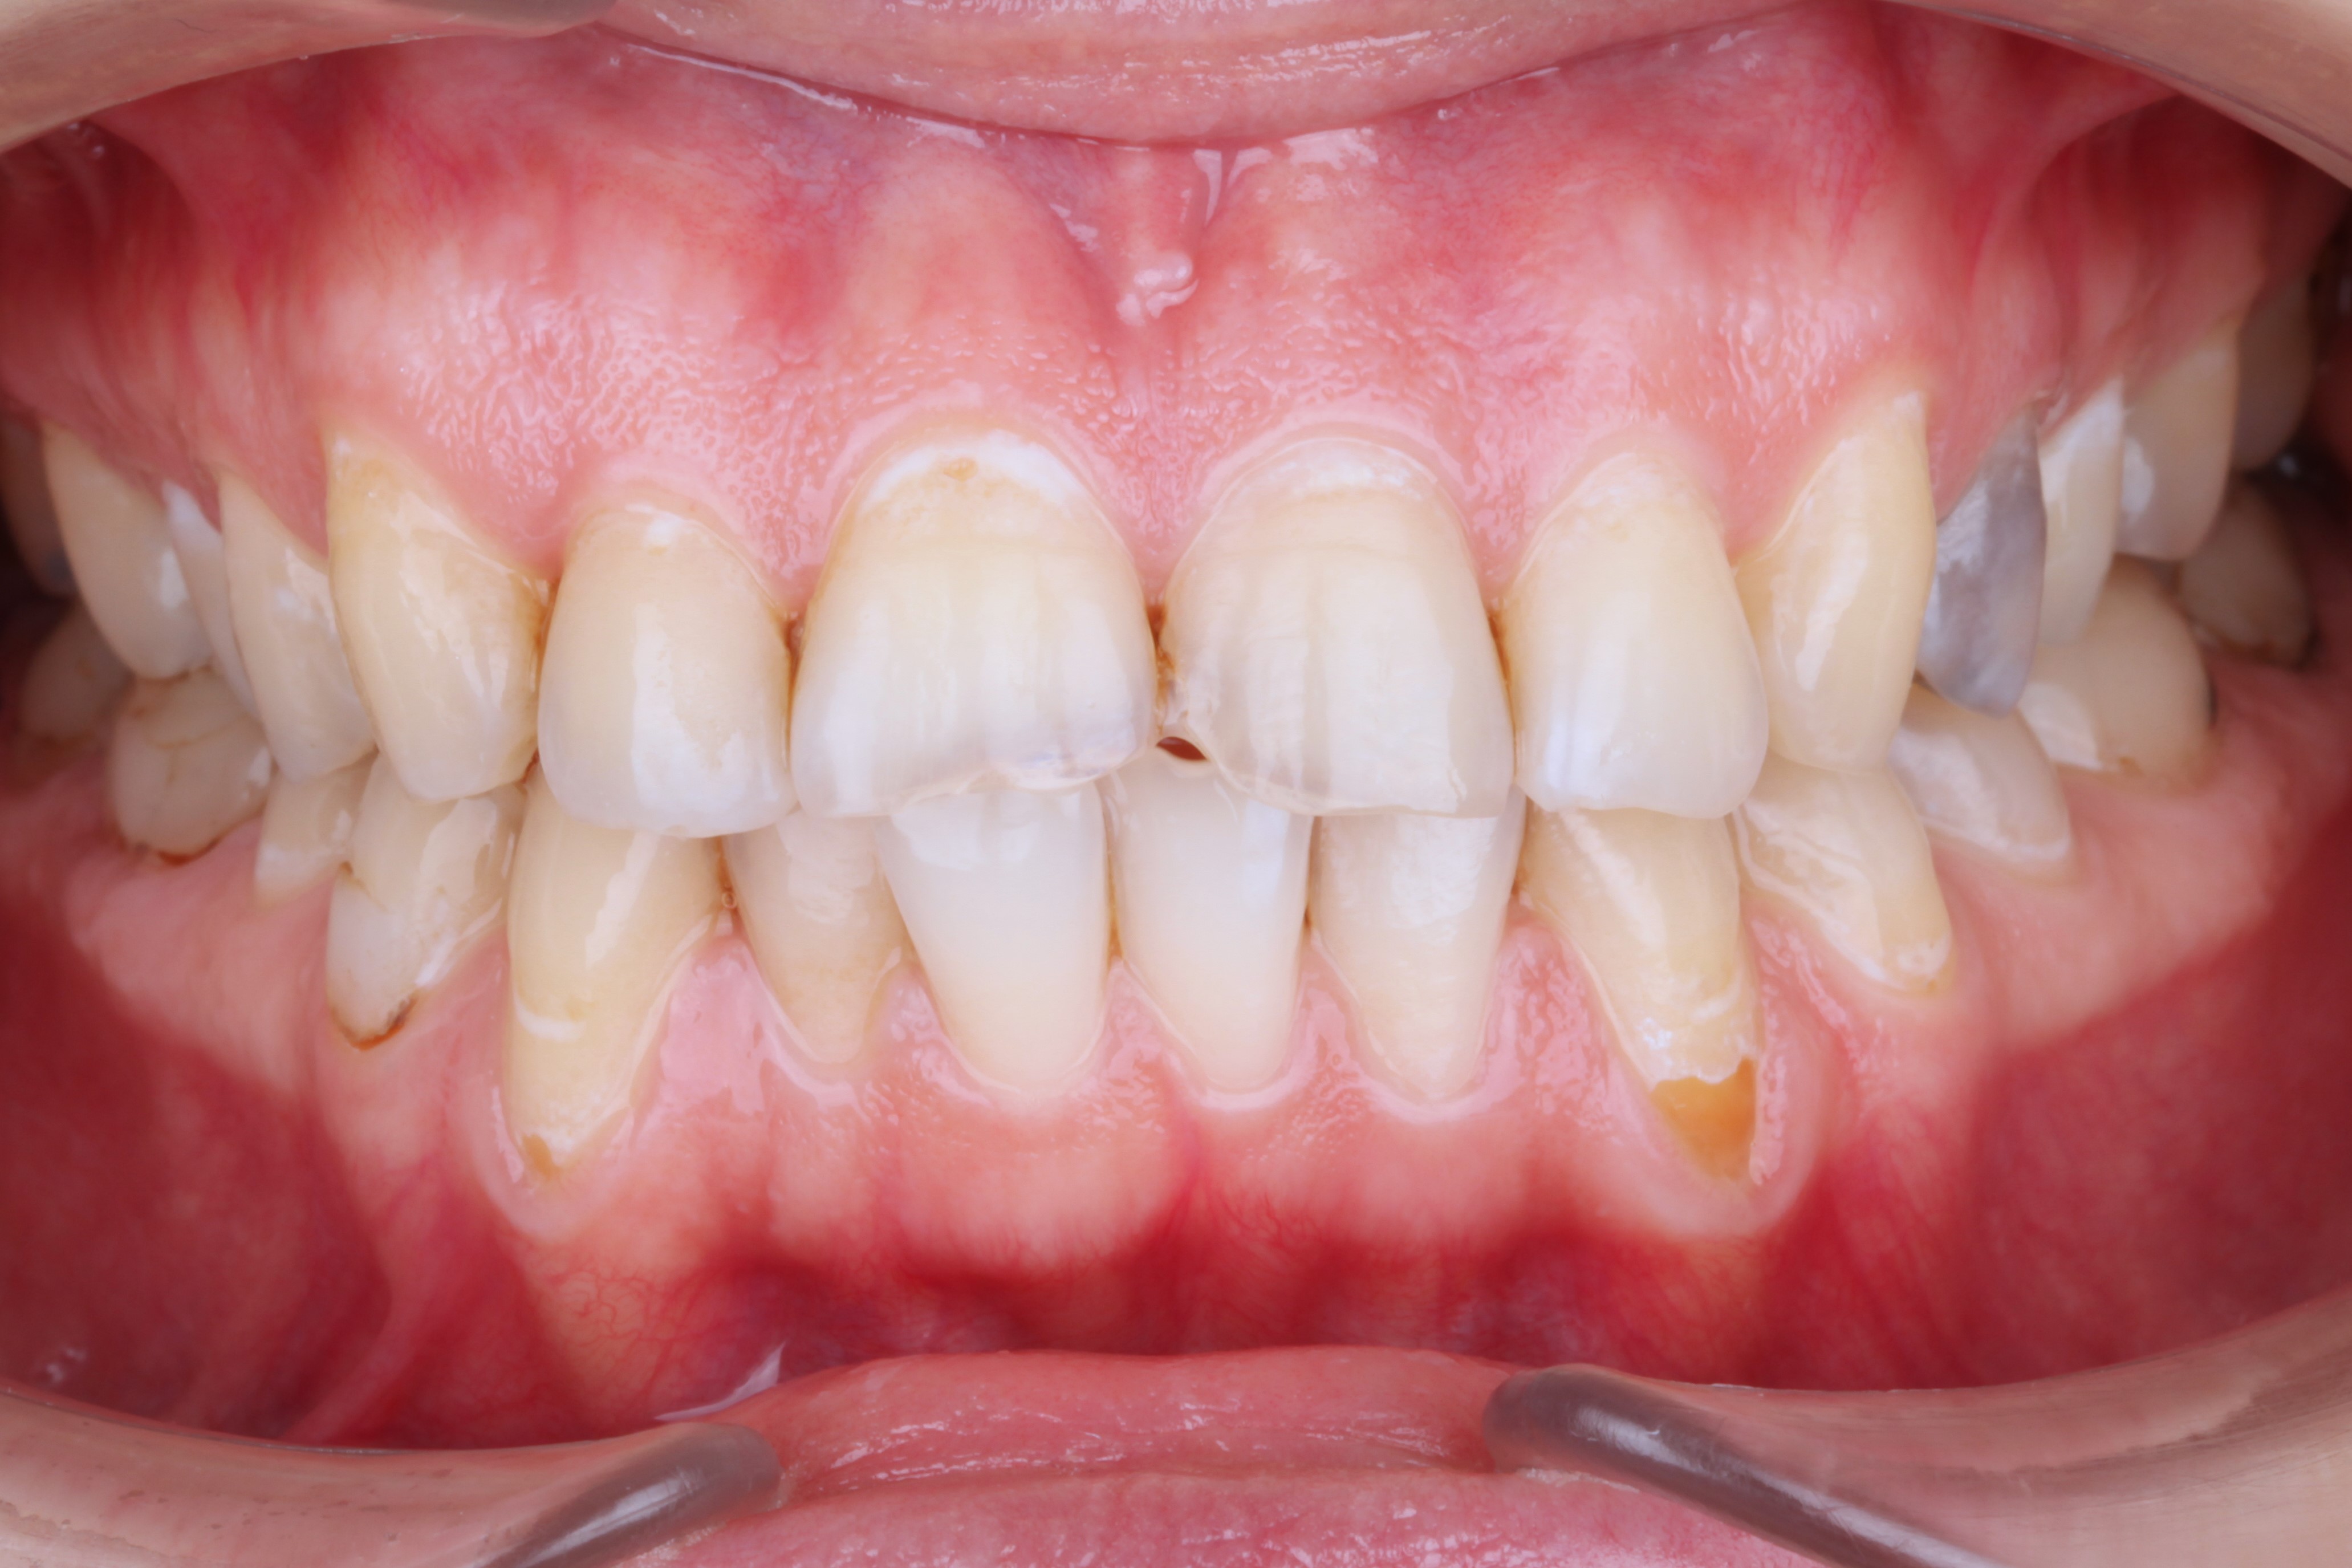

К нам обратилась пациентка 27 лет с желанием сделать красивую улыбку с ровными и красивыми зубами. На фотографии мы видим выраженные рецессии десны на нижних клыках, несостоятельные пломбы, скученность и стираемость.

В данной клинической ситуации было принято решение провести санацию полости рта, затем закрыть рецессии в области нижних клыков и только потом приступить к ортодонтии.